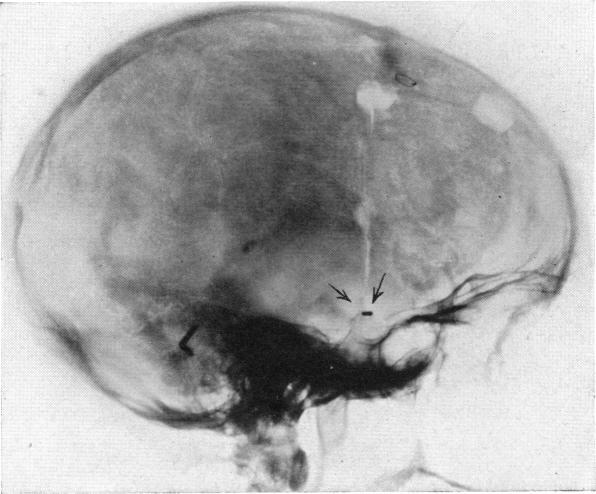

INTRACRANIAL ANEURYSM OF THE INTERNAL CAROTID ARTERY: CURED BY OPERATION.

Ann Surg. 1938 May;107(5):654-9. doi: 10.1097/00000658-193805000-00003.